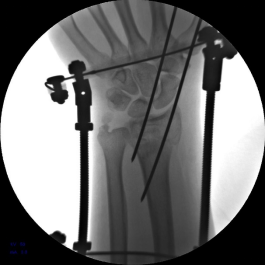

2.安装外固定架,调节螺母纵向牵拉,初步恢复桡骨高度

3.背侧穿针撬拨,继续恢复桡骨高度

7.手术完毕,复位满意